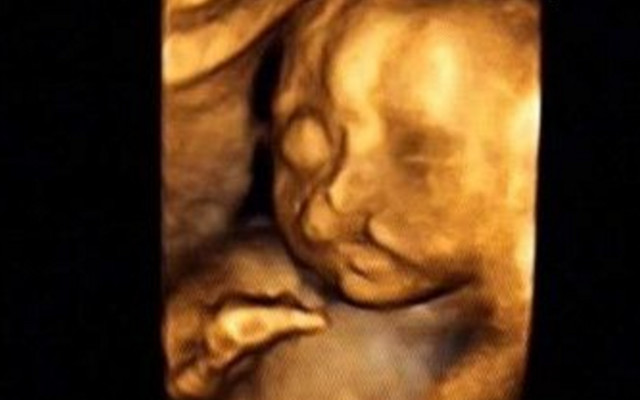

30岁的小孙就有唇裂,修补过的疤痕仍很分明。在最近一次三维B超显示,腹中的胎儿居然中度唇裂。她通知大夫,由于她诞生就有唇裂,小时老是被讪笑和厌弃。所有,无论怎样也要流掉腹中的宝宝,她不想让她的孩子再经历这样的经历。

大夫却通知小孙,现在已经孕21周,如果引产对身材损伤十分大,如果在次怀孕,不能包证就不会得唇腭裂,第二次仍会怀上唇腭裂宝宝的几率约为4%,假如怀过两次唇腭裂的宝宝,第三次怀上唇腭裂宝宝的几率会提升到14%。如今婴儿唇腭裂整形手艺,已经十分告捷,即使是重度的唇腭裂,仍是能够修补得简直看不出来了。倡议把孩子生上去,不要由于这点瑕疵,就将宝宝的性命闭幕。